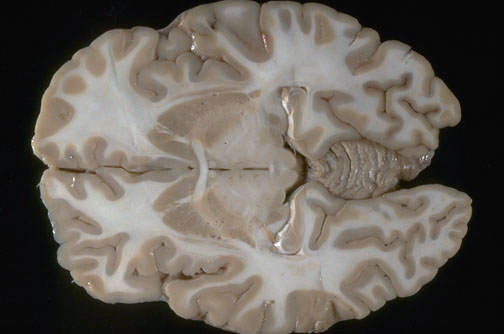

| Identify the following regions of the brain on transverse section in the image above: Anterior Commissure - Head of the Caudate Nucleus - Vermis of the Cerebellum - Superior Colliculi - Putamen - Hippocampus - Lateral Geniculate Nucleus - Medial Geniculate Nucleus - Globus Pallidus, pars lateralis - Globus Pallidus, pars medialis - Column of the Fornix - Frontal Lobe - Insular Cortex - Occipital Lobe - Temporal Lobe - Cingulate Gyrus |